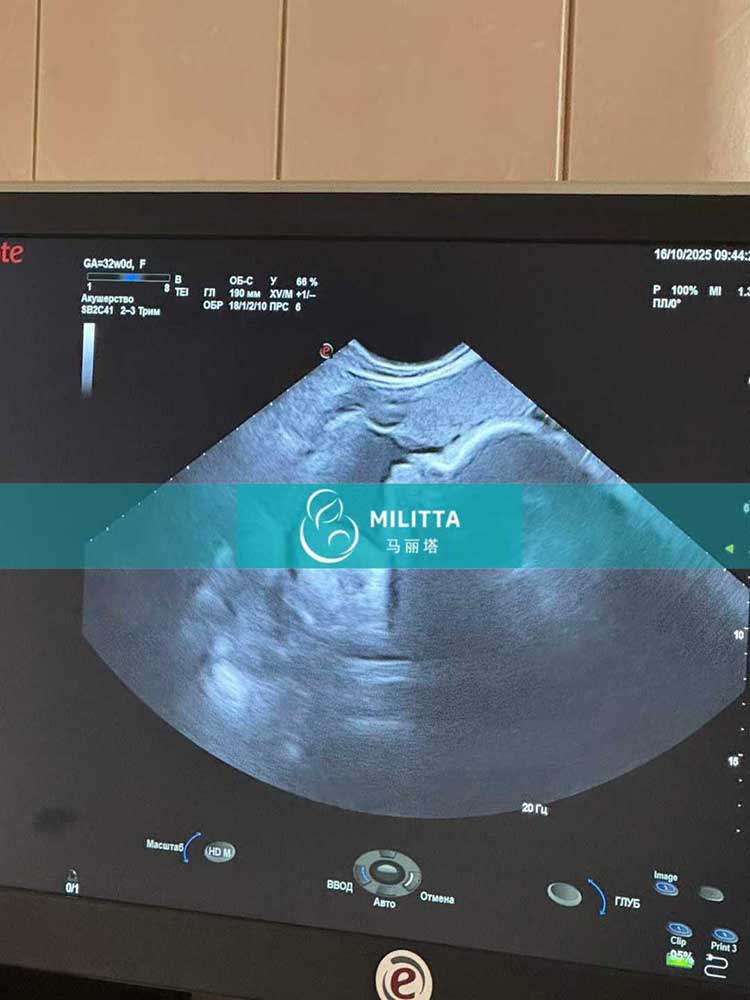

两位在乌克兰丽塔医院移植胚胎的试管妈妈在基辅做常规产检

两位在乌克兰LITA丽塔医院移植胚胎的试管妈妈在基辅做孕30周的常规产检,孕32周B超,检查胎儿状态都很好,感谢试管妈妈的照顾~